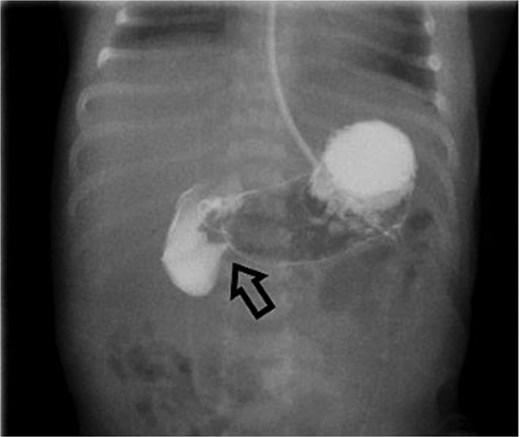

However, she returned the next day with recurrent bilious vomiting. Abdominal X-ray demonstrated a paucity of bowel gas and a fluid-filled stomach. Repeat UGI series showed delayed transit from the second to fourth portions of the duodenum, suggesting a partial obstruction (Fig. 3). Exploratory laparotomy revealed recurrent midgut volvulus with two full twists at the duodenojejunal junction. The volvulus was successfully reduced, small adhesions lysed, and no bowel resection was required. The infant recovered uneventfully in the pediatric intensive care unit and was discharged on postoperative Day 8. She has been seen in outpatient clinic and is progressing well.

Repeat UGI series reveals delayed transit from the second to fourth portions of the duodenum, suggestive of partial obstruction likely due to adhesions.